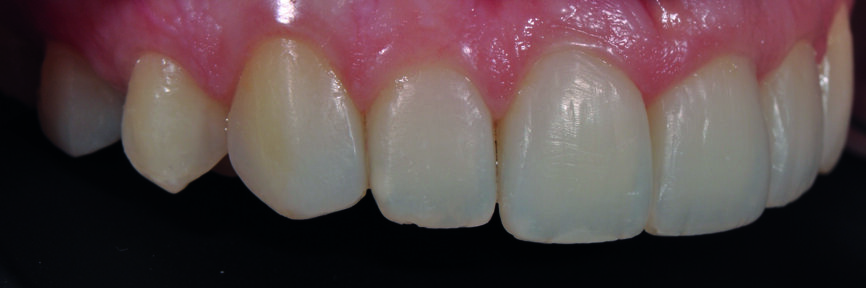

Fig. 3a : Le sourire après redéfinition de la forme des canines en incisives latérales avec le composite Essentia (GC).

Fig. 3b : Gros plan du sourire après redéfinition de la forme. Il a été possible d’obtenir un résultat très plaisant avec les restaurations composites en technique directe